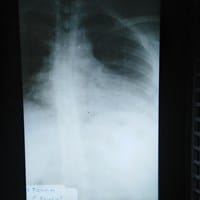

¿Alguien puede decirme el grado de corvatura que tiene mi columna? Me detectaron escoliosis leve

Me dijeron que tengo escoliosis leve, pero quisiera saber que grado tengo en mi columna, no se habrá aquí algún experto que me ayude; agregándole a eso tengo también Artritis reumatoide, y es por eso que me siento angustiada